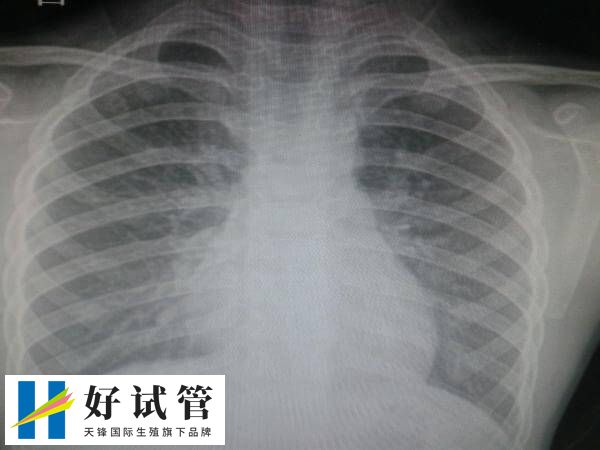

试管前做胸透为了检查什么

在进行试管婴儿前进行胸透,一般是为了排除肺部疾病,如肺结核、肺炎、肺部肿瘤等,以免不利于试管治疗期间的身体健康,其次胸部X光检查还可以了解心脏的基本情况,并查看胸廓情况,以预设后续试管婴儿助孕治疗的方案,从而确保整个试管婴儿过程的安全性。

试管拍胸片检查的目的

胸透作为临床常见的检查之一,尤其是作为健康体检的常规项目之一,也是做试管拍胸片是常规体检项目之一,一般做试管婴儿前进行胸透检查,是为了排除身体是否存在疾病,如果有患者对此比较感兴趣,可参考下列内容:

1、排除肺部疾病

患者做试管婴儿前期检查拍胸部x光,主要是排除肺部疾病的发生,如肺结核、肺炎、肺部肿瘤等疾病,以及胸部器官的基础疾病,bij这些疾病可能会影响试管婴儿的进程和孕妇的健康。

2、评估心脏情况

在进行试管婴儿前进行胸透(胸部X光检查),也可以评估心脏情况,比如可以评估心脏的大小和形态,了解心脏的基本情况,排除心脏疾病对妊娠的潜在影响。

3、术前常规检查

胸透检查可以作为术前的常规检查项目,为后续的治疗和手术提供参考依据,确保整个试管婴儿过程的安全性。